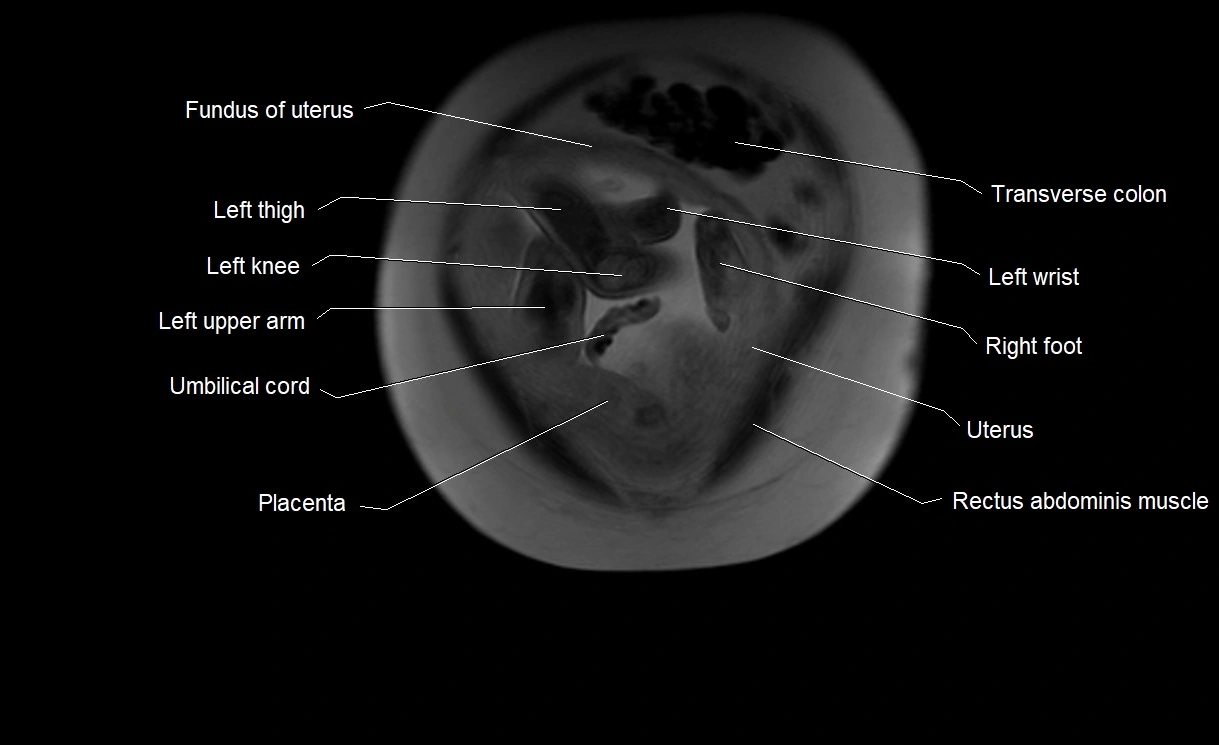

MRI Appearance

T2 HASTE (T2 GRE):

• Amniotic fluid shows very bright hyperintense signal

• Provides natural contrast against fetus and placenta

• Small particles (vernix) may appear as scattered hypointense foci within bright fluid

MRI image

image